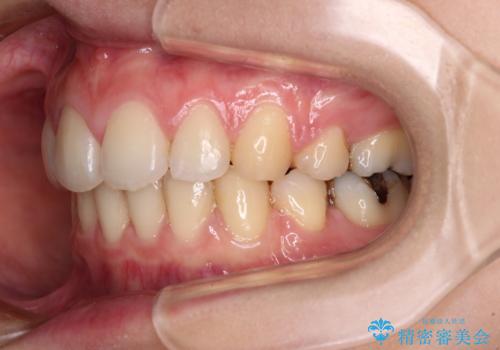

- 口元の突出感と口の閉じにくさを気にして来院された患者様です。

上下左右第一小臼歯4本を抜歯し、ワイヤー装置にて口元を引っ込めるよう矯正治療を行うこととしました。

ご友人などがびっくりするほど口元の突出感を改善することができ、患者様には大変満足していただきました。